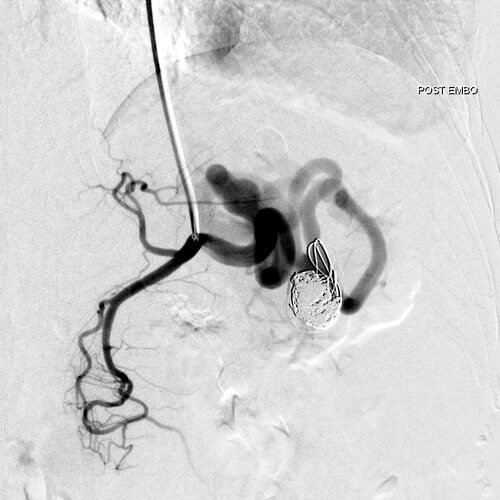

45 year old female patient who presents with ill-defined abdominal pain. A CT demonstrated a splenic artery aneurysm. Treatment was attempted from a femoral approach but the tortuosity of the splenic artery made it impossible to maintain a stable catheter position. As a result, radial access was obtained, and embolization was ultimately performed with multiple detachable coils.

Comment: This case demonstrates the importance of choosing the most appropriate access site given the demands of the procedure. In this case, the angle of the celiac axis favored a radial approach. By placing the sheath from a radial approach, the system was stable until the first curve of the celiac axis. The presence of the sheath enabled us to push the microcatheter forward in the splenic artery without buckling the sheath into the aorta. Ultimately, the microcatheter was advanced until it coiled within the aneurysm. Care was taken while embolizing to keep the coils more towards the inferior aspect of the aneurysm sac to maintain patency of the vessel arising from the apex of the aneurysm.